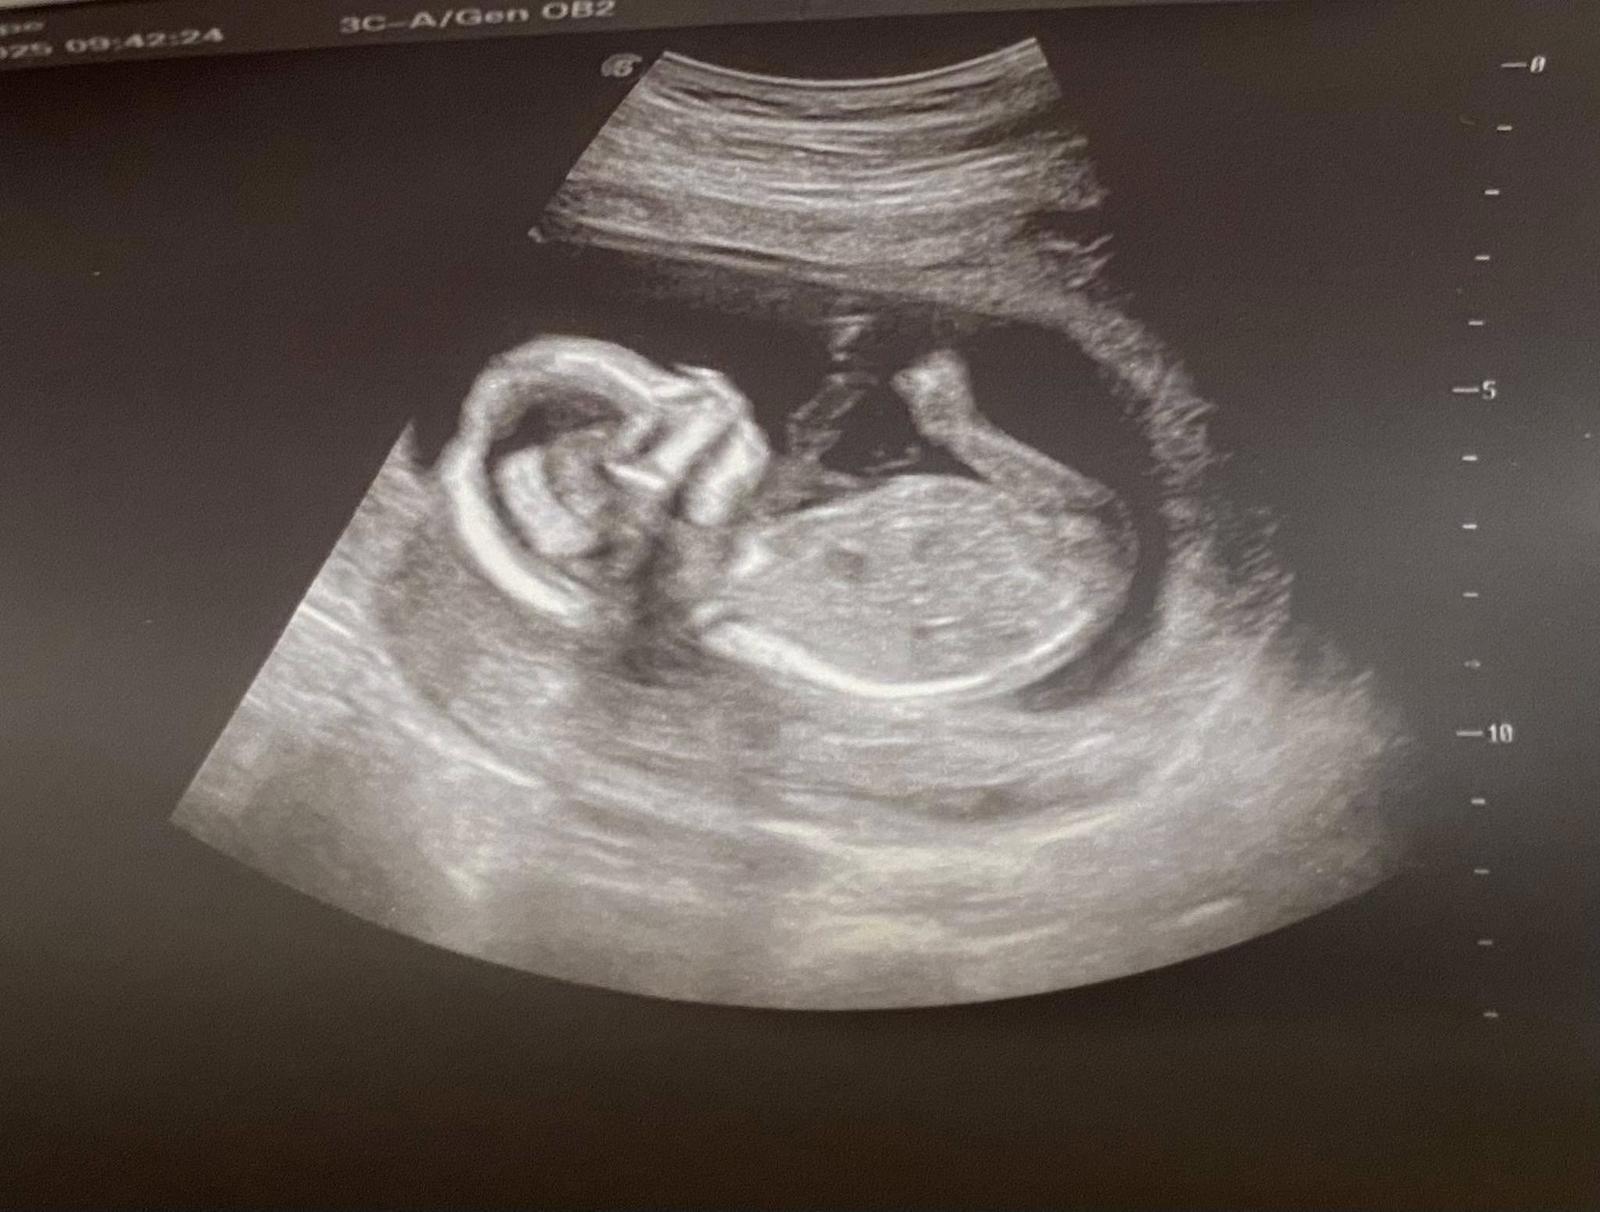

Dobrý den. Na ultrazvuku byl vidět ,, pindík, vrchem a stal🙈 Doktor řekl že tipuje kluka a za 3 tydny to pry bude vidět líp. Mam doma 4 holky🙈🤣 nepoznáte to Podle hrbolku nějakého? 🙈

Bude to krasne miminko…. Pahorek neni videt…